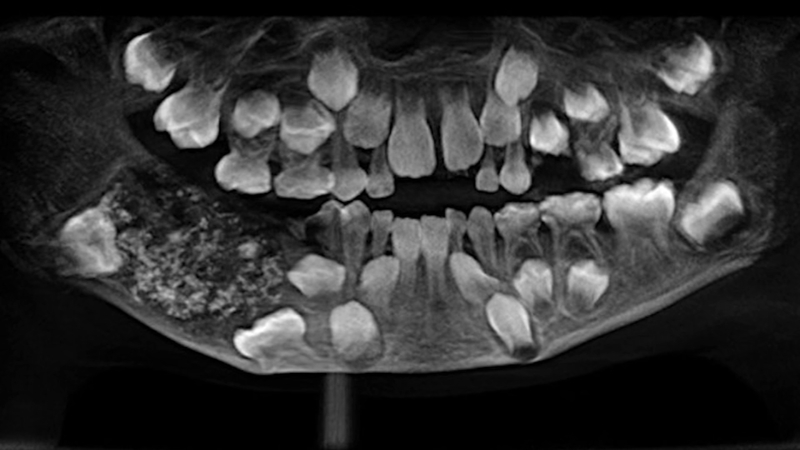

Saveetha牙科医学院的一组外科医生从一名7岁男孩的右下颚切除了一个包含526颗“牙齿”的肿块。这个近200克重的庞然大物里面有许多细小的牙齿,还有几颗中、大牙齿。

医院的医生拍了一张x光片,显示出肿块内有许多小的未发育的“牙齿”。口腔颌面外科教授森提尔内森说:“CT扫描显示,多颗“牙齿”将恒牙推到了下颚。我们计划采取保守治疗,不切除颌骨。”他补充说,16年后,这名男孩将需要植入两颗恒磨牙。

“我们把肿块像袋子一样切开,之后我们确定了牙齿结构,发现里面有珐琅质。在立体显微镜下,我们看到了最小的“牙齿”。在此之前,我们最多只看到过26颗牙齿。”另一名医生拉马尼博士说。